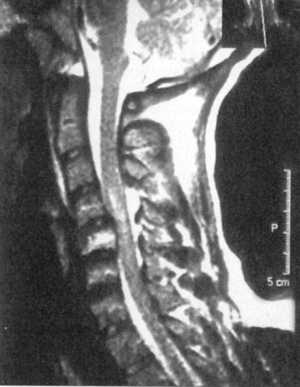

Ценную информацию о состоянии вывихнутых позвонков и спинного мозга дает

МРТ (рис. 2.6, 2.7). МРТ позволяет определить наличие зон ишемии в спинном

мозге (рис. 2.8, 2.9), состояние ликвородинамики (рис. 2.10).

Рис. 2.8. Компрессионный перелом с подвывихом кзади С4 позвонка

с зоной ишемии спинного мозга

Рис. 2.9. Вывих С4-С5, позвонков с зоной ишемии спинного мозга